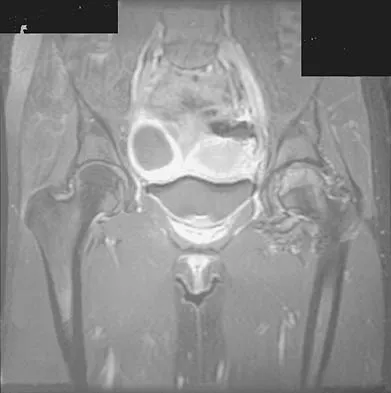

Figures 1a through 1c show the radiograph and MRI scans of a 16-year-old patient who has a painful hip. Examination reveals a significant limp, limited abduction and internal rotation, and severe pain with internal rotation and adduction. A biopsy specimen is shown in Figure 1d. What is the deposited pigment observed in this condition?

Explanation

Pigmented villonodular synovitis (PVNS) is a synovial proliferative disorder that remains a diagnostic difficulty. The most common clinical features are mechanical pain and limited joint motion. On radiographs, the classic finding is often a large lesion, associated with multiple lucencies. Other findings may include a normal radiographic appearance, loss of joint space, osteonecrosis of the femoral head, or acetabular protrusion. MRI is the imaging modality of choice and will show the characteristic findings of a joint effusion, synovial proliferation, and bulging of the hip. The synovial lining has a low signal on T1- and T2-weighted images, secondary to hemosiderin deposition. Copper deposition occurs in patients with Wilson's disease, which mainly affects the liver. Bhimani MA, Wenz JF, Frassica FJ: Pigmented villonodular synovitis: Keys to early diagnosis. Clin Orthop 2001;386:197-202.